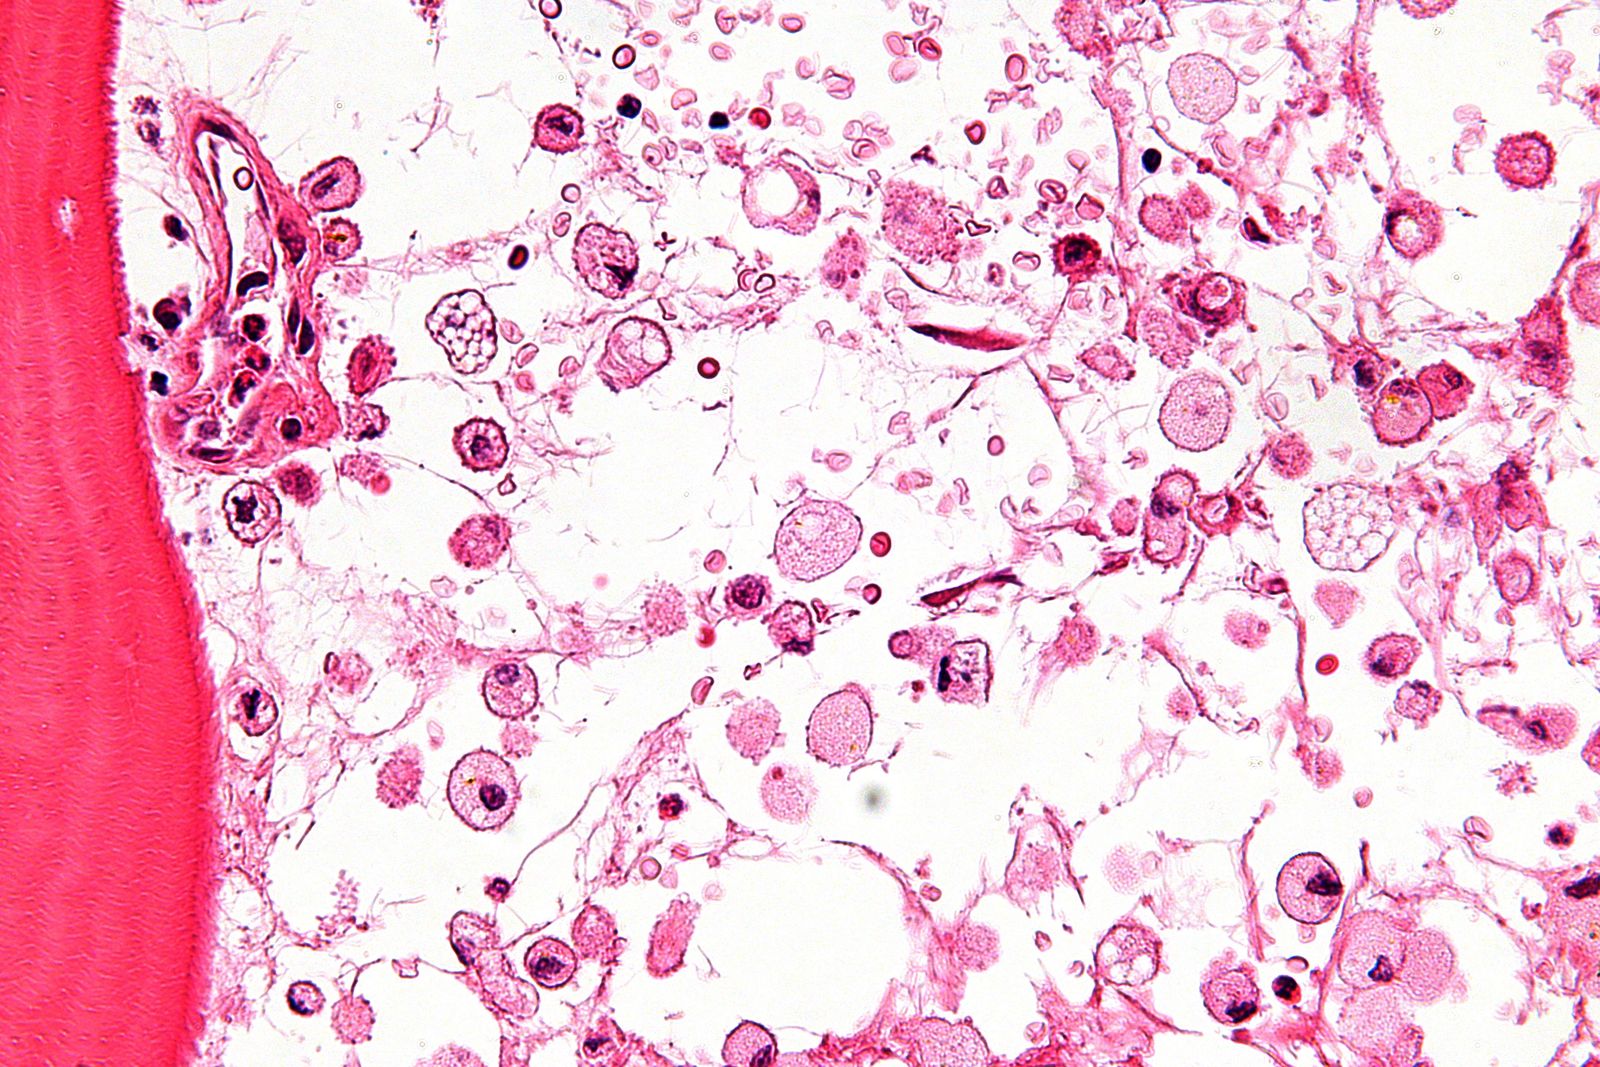

Gošē slimība rodas, ja organismā ir konkrēta enzīma – glikocerebrozidāzes deficīts. Šī enzīma uzdevums ir sašķelt specifiskus lipīdus (tauku substanci) – glikocerebrosīdus. Slimības gadījumā enzīma nepietiekamības vai neesamības dēļ glikocerebrosīdi netiek sašķelti un lizosomās uzkrājas lipīdi. Tas ir līdzīgi kā mājsaimniecībā, kad atkritumu maisi netiek izvesti, bet ir tik daudz, ka tie krājas jau ārpus miskastes. Ar laiku šie atkritumi aizņem daudz vietas un rada virkni problēmu. Tāds pats princips darbojas cilvēka šūnām – tā kā organismam nav citas iespējas kā atbrīvot lizosomas no lipīdiem, enzīmu trūkuma dēļ šūnas palielinās. Šādas, lipīdu dēļ, palielinātas šūnas sauc par Gošē šūnām.